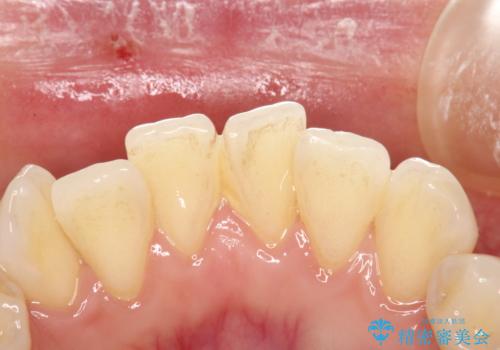

- 約3か月ごとにPMTCを行っている方です。定期的にメンテナンスしているためPMTC30分コースで全体のクリーニングが可能でした。

歯の表面は磨けていても、歯茎の境目や歯と歯の間の磨き残しはとても多いです。そのため、定期的にメンテナンスを行い、どこに磨き残しがあるか確認したり、歯磨きの仕方について指導を受けることが大切です。